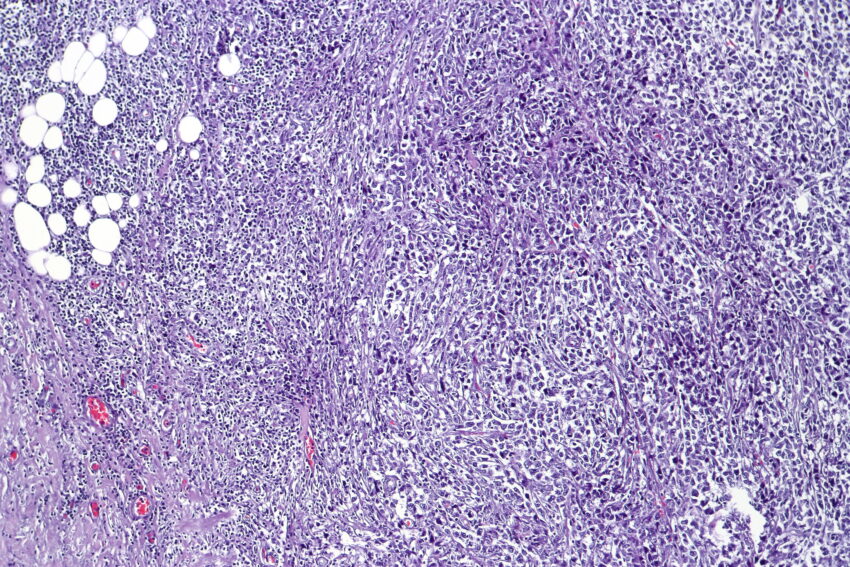

Diffuse large B-cell lymphoma (DLBCL) is the most common type of non-Hodgkin lymphoma in adults worldwide, accounting for around 30% of newly diagnosed cases. It is an aggressive (fast-growing) type of blood cancer. It responds well to initial chemotherapy in many people but relapse is common.